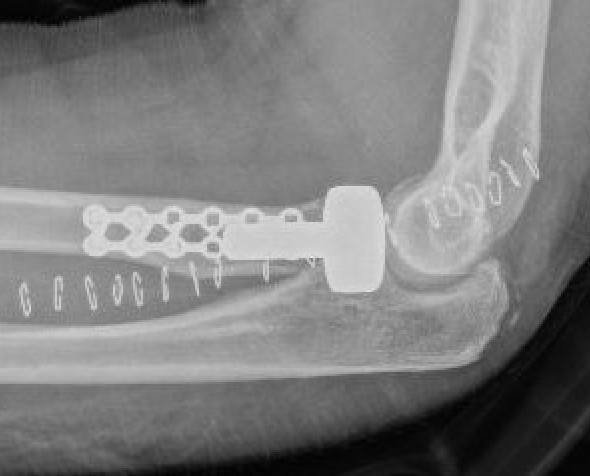

ORIF with plates

Lateral approach

- identify safe zone (90 degrees between radial styloid) and Lister's tubercle)

- lag articular surface first if required

- pre-contoured low profile plates

- distal limit is bicipital tuberosity

- check ROM intra-operatively

- plates often bulky and may limit ROM

- close annular ligament